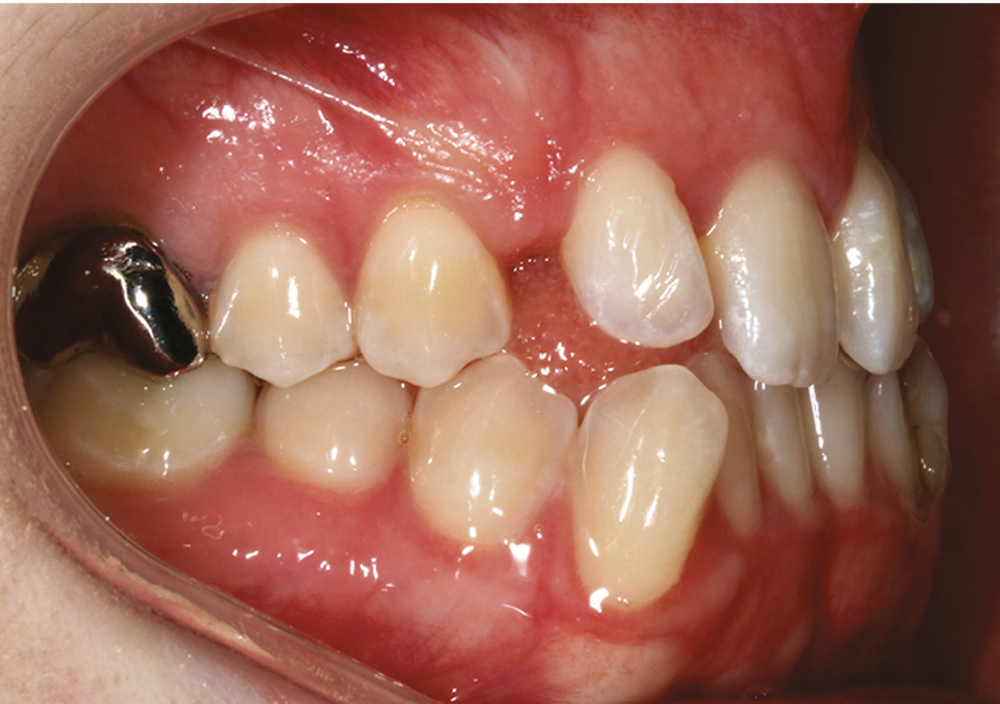

La patiente, âgée de 24 ans, en bonne santé générale, consulte en orthodontie pour raisons esthétiques. Elle présente une classe III squelettique par rétrognathie maxillaire sur un schéma facial hyperdivergent (fig. 1a-b).

Sur le plan dentaire, on note l’absence des canines maxillaires permanentes sur l’arcade et la persistance de 63. Il existe une DDD par défaut maxillaire (indice de Bolton antérieur 90,2 %) due à l’absence des canines sur l’arcade, mais aussi à une dysharmonie de forme des dents maxillaires (fig. 2a-e).

Sur le plan fonctionnel, la patiente présente une déglutition atypique associée à une posture linguale basse.